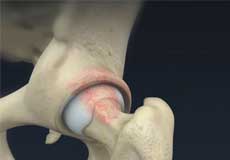

Hip Cartilage Repair

Hip cartilage is a white, tough, flexible tissue covering the ball (femoral head) and socket (acetabulum) of your hip joint. It acts as a cushion or shock-absorber and allows the bones to slide over one another by providing a smooth surface in the joint.

Articular cartilage is the thin, tough, flexible, and slippery surface lubricated by synovial fluid that covers the weight-bearing bones of the body. It enables smooth movements of the bones and reduces friction.